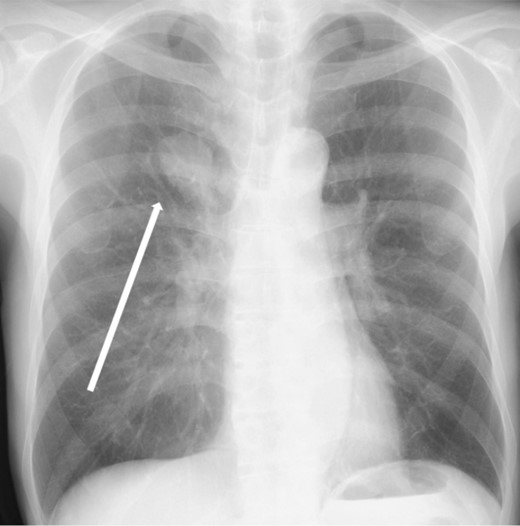

The patient was a 73-year-old man. He had a history of arteriosclerosis obliterans in the lower extremities, transient atrial fibrillation, and was consuming two antiplatelet agents. The patient had a fever within the range of 38°C. Blood tests showed an elevated white blood cell (WBC) count of 31.6 × 103/μl (neutrophil, 90.2%), CRP of 9.67 mg/dl, and APTT of 125.4 s. Chest radiography revealed an abnormal shadow in the upper lobe of the right lung (Fig. 1). Contrast-enhanced chest CT revealed an irregularly shaped mass, 43 × 33 × 28 mm in size, in the upper lobe of the right lung (Fig. 2). 18F-fluorodeoxyglucose-positron emission tomography showed abnormal accumulation with a maximum standardized uptake value of 28.4 in a pointed lesion in the upper lobe of the right lung (Fig. 3). A bronchoscopic biopsy was performed, and the patient was diagnosed with non-small cell carcinoma.

18F-fluorodeoxyglucose positron emission tomography findings. Abnormal accumulation of Max SUV 28.4 was found in a pointed lesion in the right upper lobe of the lung, which was considered to be a primary lung cancer site.